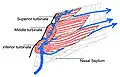

In humans, the conchae divide the nasal airway into four groove-like air passages, and are responsible for forcing inhaled air to flow in a steady, regular pattern around the largest possible surface area of nasal mucosa. As a ciliated mucous membrane with shallow blood supply, the nasal mucosa cleans and warms the inhaled air in preparation for the lungs.

The middle conchae are smaller but have the most complex anatomy of the nasal turbinates. They originate from the lateral edge of the cribriform plate of the ethmoid bone. They insert anteriorly into the frontal process of the maxilla and posteriorly into the perpendicular plate of the palatine bone.[6] There are three mutually perpendicular segments of the middle turbinate: from proximal to distal, there is the horizontal segment (axial plane), the basal lamella (coronal plane), and the vertical segment (sagittal plane). They project downwards over the openings of the maxillary and anterior and middle ethmoid sinuses, and act as buffers to protect the sinuses from coming in direct contact with pressurized nasal airflow. Most inhaled airflow travels between the inferior concha and the middle meatus.[3] In humans, they are usually as long as the little finger.

The inferior conchae are the largest turbinates, can be as long as the index finger in humans, and are responsible for the majority of airflow direction, humidification, heating, and filtering of air inhaled through the nose.[3]

The conchae are also responsible for filtration, heating, and humidification of air inhaled through the nose. Of these three, filtration is achieved mostly by other more effective means such as mucous and cilia. As air passes over the conchae, it is heated to 32–34 °C (89–93 °F), humidified (up to 98% water saturation) and filtered.[4]

The conchae provide, first and foremost, the humidity needed to preserve the delicate olfactory epithelium, which in turn is needed to keep the olfactory receptors healthy and alert. If the epithelial layer gets dry or irritated, it may cease to function. This is usually a temporary condition but, over time, may lead to chronic anosmia.[4] The turbinates also increase the surface area of the inside of the nose, and, by directing and deflecting airflow across the maximum mucosal surface of the inner nose, they are able to propel the inspired air. This, coupled with the humidity and filtration provided by the conchae, helps to carry more scent molecules towards the higher, and very narrow regions of the nasal airways, where olfaction nerve receptors are located.[3]